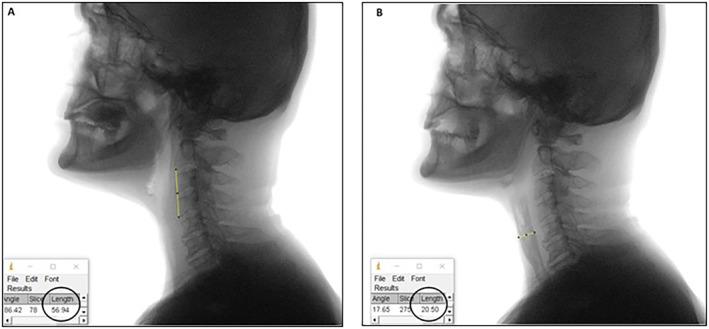

A total of 34 subjects with TL were included in the study. Swallowing kinematics of those with symptomatic swallowing complaints (Group 1) were compared to those without (Group 2). Kinematic parameters including pharyngeal transit duration (PTD), maximum pharyngeal constriction ratio (MPCR), upper esophageal sphincter opening ratio (UESOR), upper esophageal sphincter opening duration (UESOD), and bolus clearance ratio (BCR) were investigated from Videofluoroscopic Swallowing Study (VFSS) records via ImageJ software.

本研究共纳入34例全喉切除术患者。将有吞咽症状性主诉的患者(第1组)的吞咽运动学与无此主诉的患者(第2组)进行比较。通过ImageJ软件从视频荧光吞咽造影研究(VFSS)记录中调查包括咽部通过时间(PTD)、最大咽部收缩率(MPCR)、食管上括约肌开放率(UESOR)、食管上括约肌开放持续时间(UESOD)和食团清除率(BCR)在内的运动学参数。